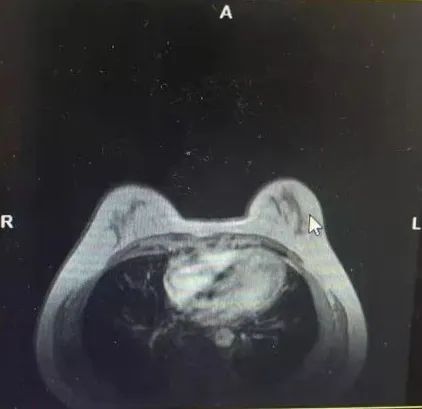

·乳腺彩超

1、右乳9点见一个低回声区,大小约0.53*0.63cm,呈直立生长,边缘成角、毛刺,内部回声不均匀,肿块内未见强回声,BIRADS 5类;

2、右乳10点见一个低回声区,大小约1.4*0.9cm,边缘成角、毛刺,内部回声不均匀,肿块内未见强回声,BIRADS 5类。

图1乳腺彩超结果